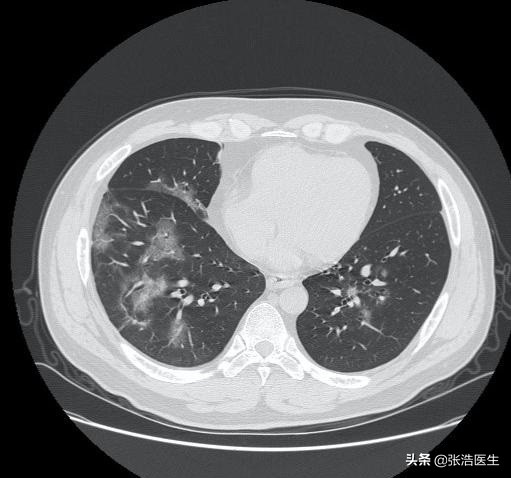

(上图是冠状病毒肺炎的胸部CT图像)

普通肺炎会出现发热,而新型冠状病毒感染导致的肺炎也会出现发热,所以很多人想从发热入手来区别普通肺炎和新型肺炎,一般情况性病毒性肺炎往往因为潜伏期时间比较长,所以在早期往往会有长时间的低烧阶段,而细菌性的肺炎往往进展比较快,而且一旦形成大叶肺炎会出现明显的高热。

但是单纯的依靠发热是无法准确诊断这两者的。两者还有很多的相似之处,如咳嗽、咳痰等,尤其是老年性的肺炎,也会出现呼吸困难等,这一点更难和新型肺炎区别。

就目前公布的情况来看,单纯的从发热症状来看,无法完全的区别的新型肺炎和其他的肺炎,建议出现咳嗽、呼吸困难、发热症状的人群,尤其是有武汉接触史的,尽早上报隔离,必要时就诊发热门诊及时治疗,为自己考虑也为周围的人考虑。#疫情之下,我的日常生活# #关注新型肺炎# #清风计划# @清风计划 @头条健康